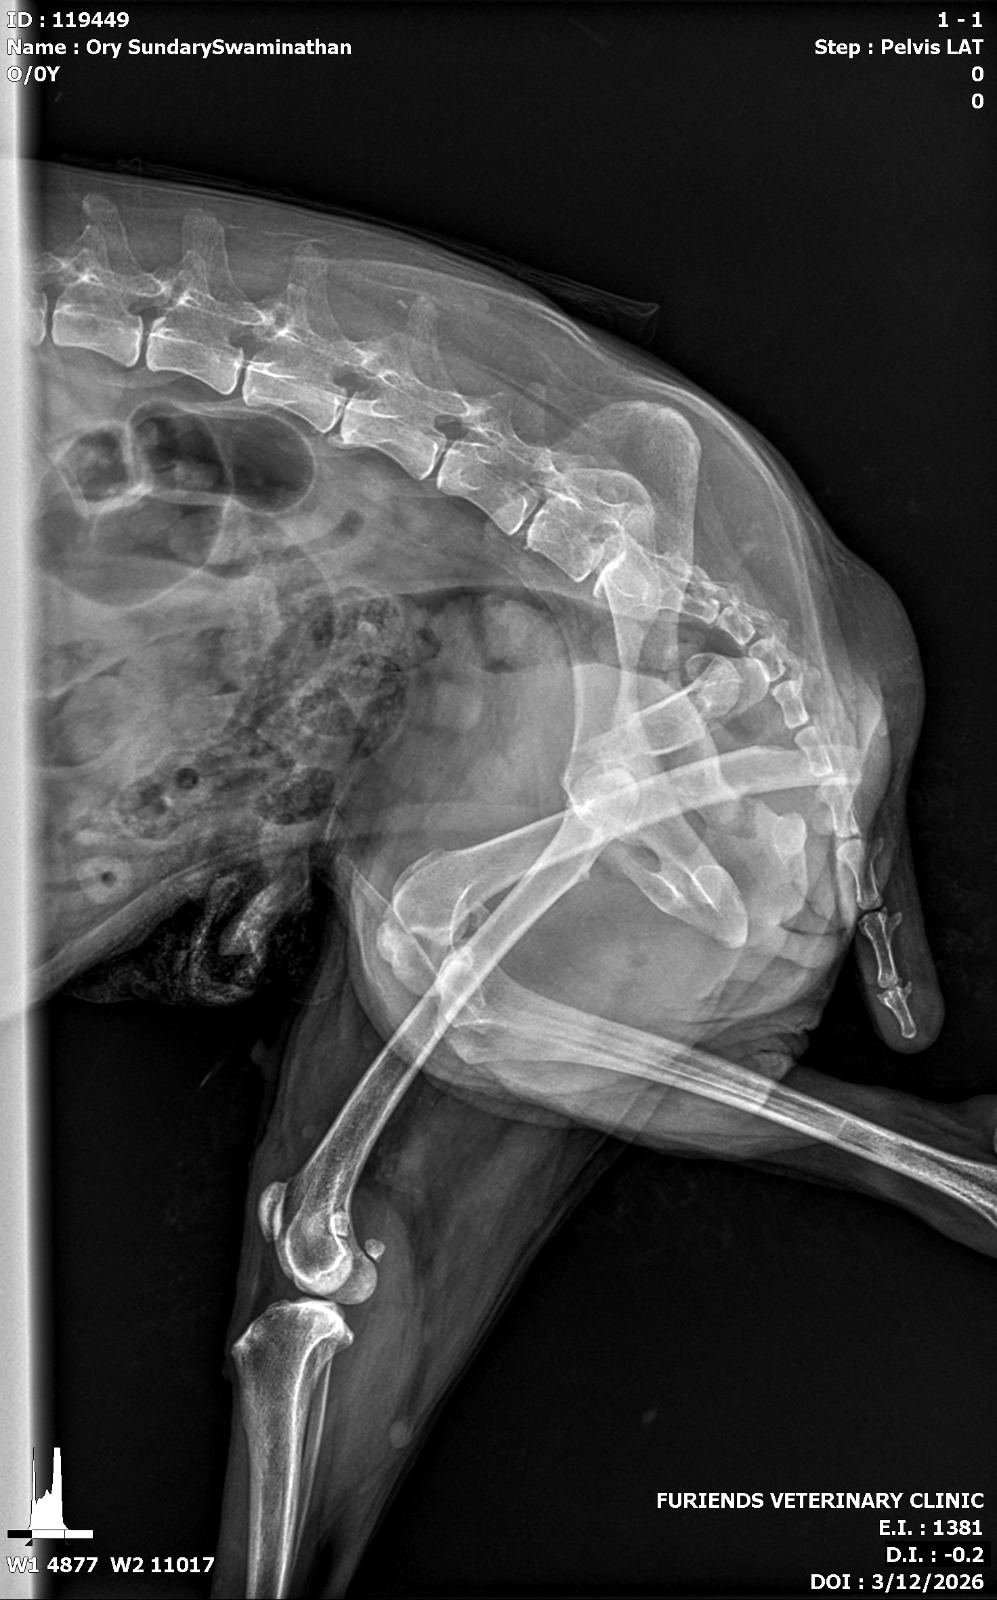

I returned to Singapore after a long trip, spending the 13-hour flight mentally preparing myself for the next phase of my life—career growth, personal goals, and how I was going to move forward. More than anything, I couldn’t wait to pick up Ory from the boarding home I had left him at. I knew he wasn’t walking, but I assumed it was just his usual leg cramp. Little did I know, a huge shock was waiting for me. The moment I saw him, my heart sank—his leg looked broken, and deep down I knew something was very wrong. The Ory who loved to walk was struggling to even take a step, yet he kept trying. I held onto hope that it was just a muscle or ligament issue, but the next day, I rushed him to the nearest vet where an X-ray confirmed my worst fear: a broken femur.

Ory xray Ory xray1

I was given two options—amputation or putting him down. My world was shaken. The vet explained that due to his age, arthritis, and weak remaining legs, there was no guarantee he would be able to walk again after amputation. It all came down to his quality of life. I was referred to a specialist, and thankfully, I managed to get an appointment that very same day. The specialist echoed the same options but gave me a glimmer of hope—despite his injury, Ory was still trying to move, still fighting. He was placed on a fentanyl patch to manage the pain, but that night, he reacted badly, becoming extremely vocal and uncomfortable.